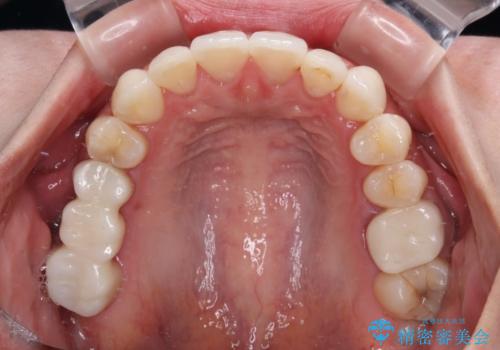

ワーキングホリデー前にきれいな歯列に

- 2、3年後にワーキングホリデーで海外に行くため、その前に歯列やむし歯をきれいにしたいとのことで来院された患者様です。

抜歯の必要な右上の奥歯は事前に抜歯をし、インビザラインにて上下歯列を整えることとしました。

矯正治療後半に奥歯の補綴治療が必要な歯にはオールセラミッククラウンを装着し、インビザラインで最終的に仕上げることとしました。